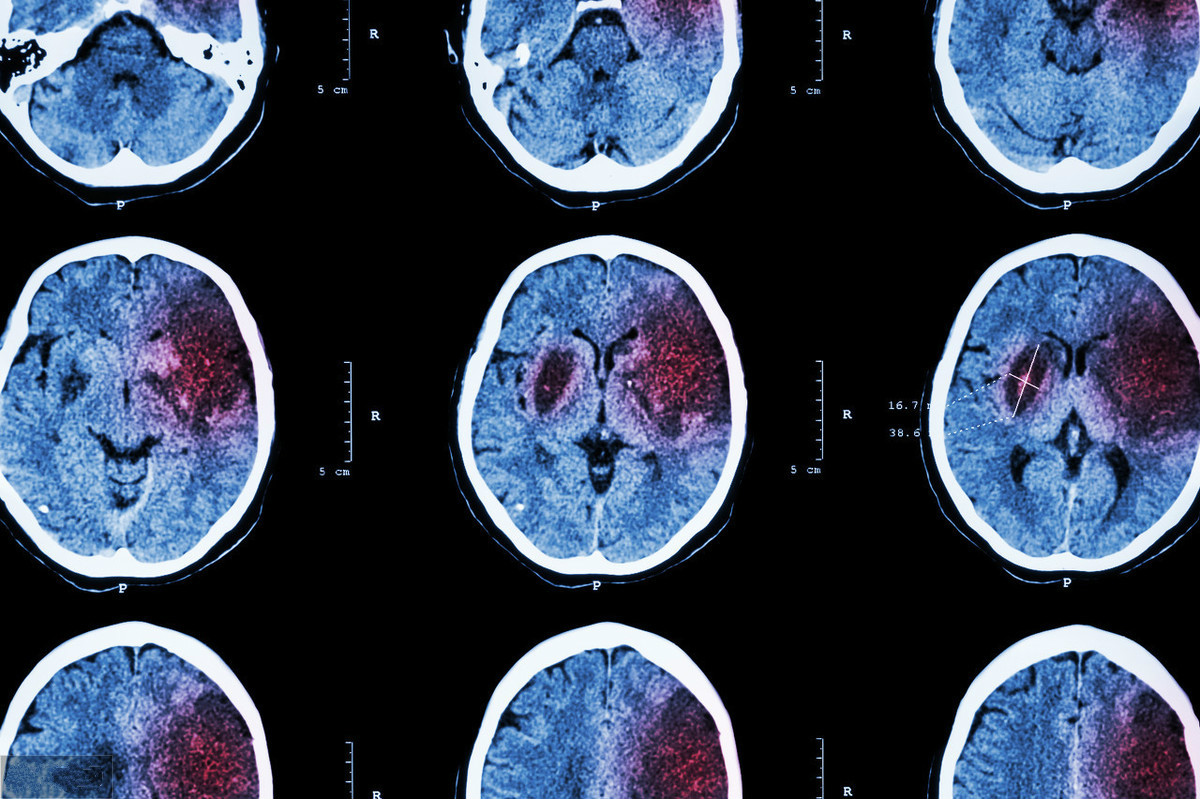

腦血管疾病是由腦血管本身的病變和血流循環(huán)障礙引起的腦功能障礙的一組疾病,分急性腦血管病和慢性腦血管病。那么腦血管疾病種類的癥狀有哪些呢?

腦血管病有兩種類型,即出血性腦血管病和缺血性腦血管病。

出血性腦血管病包括腦動脈瘤、動靜脈畸形、海綿狀血管瘤、高血壓腦出血等等。對于出血性疾病,比如高血壓、腦出血、動脈瘤、動靜脈畸形,表現(xiàn)為出現(xiàn)嚴(yán)重的頭痛、頭昏、惡心、干嘔等顱內(nèi)壓增高癥狀。同時多數(shù)患者存在一定程度顱神經(jīng)功能障礙,表現(xiàn)為出現(xiàn)口齒不清、言語不利、偏癱、運(yùn)動型失語等臨床表現(xiàn)。

缺血性腦血管病主要包括腦梗塞、腦血管狹窄、慢性的血管閉塞等。對于缺血性疾病、腦梗死,還會表現(xiàn)為出現(xiàn)一側(cè)肢體麻木、疼痛、感覺異常。

當(dāng)患者出現(xiàn)上述癥狀時,及時就診于神經(jīng)內(nèi)科進(jìn)行頭顱CT、頭顱核磁平掃加血管掃描、頭顱血管CTA,甚至選擇腦血管造影等相關(guān)檢查,進(jìn)行血糖、血脂、肝腎功能等相關(guān)檢查,明確病因以后及時治療,患者自身要控制好血糖、血脂、血壓等基礎(chǔ)疾病,配合治療。